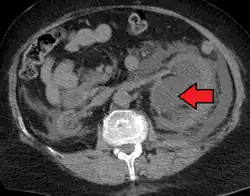

CT scan of bilateral hydronephrosis due to a bladder cancer -